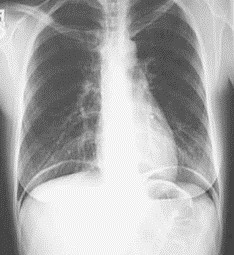

Mężczyzna w wieku 48 lat zgłosił się do izby przyjęć szpitala z powodu nagłego silnego bólu w nadbrzuszu. W badaniu fizykalnym stwierdzono żywą bolesność z obroną mięśniową i objawem otrzewnowym w nadbrzuszu, śródbrzuszu i podbrzuszu. Tętno i ciśnienie tętnicze wynosiły odpowiednio 120/min i 100/60 mmHg. W badaniach laboratoryjnych krwi stwierdzono WBC 18,3 K/µL, stężenie amylazy 85 U/L, stężenie lipazy 42 U/L, CRP 183 mg/dL, stężenie bilirubiny 0,56 mg/dL. W badaniach obrazowych jamy brzusznej stwierdzono bezkamiczy pęcherzyk żółciowy, PŻW szerokości 5 mm oraz niejednorodną trzustkę o prawidłowych wymiarach z obecnością wolnego płynu w górnych obszarach jamy otrzewnej. Wynik badania radiologicznego klatki piersiowej przedstawiono na rysunku. Jakie postępowanie należy zaproponować u tego chorego?